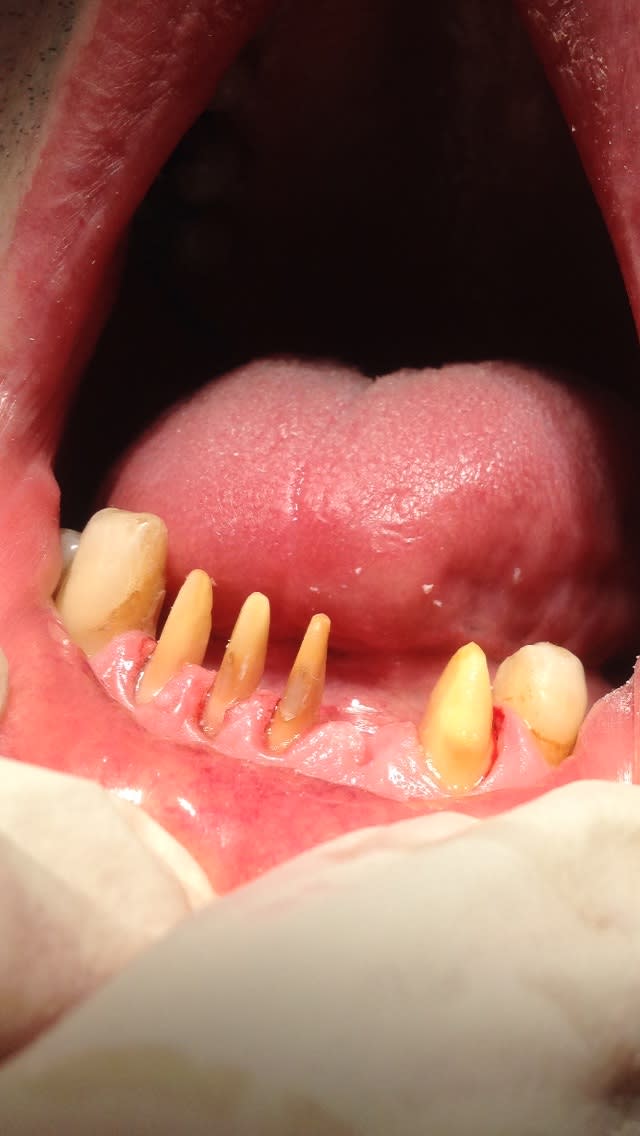

-> regardez voir la magnifique langue que j'ai sur la 2eme photo

Img 0663 lvswpo - Eugenol

Img 0660 vclvgo - Eugenol

" -> regardez voir la magnifique langue que j'ai sur la 2eme photo "

ce que l'on peut voir ç est que ce n'est pas forcement un pb de langue majeur .

tu vois les points sur la lèvre inf ?

elle compense sa cl2 en se mordant la lèvre inf . si ç est ça ,le bourrelet dont je parlait ,elle le ferait ,non pas avec la langue ,mais avec sa lèvre inf . la pression sur les dents du haut seraient dues à la levre inf et non pas forcement à la langue .

ç etait comme ça avant les prov ?